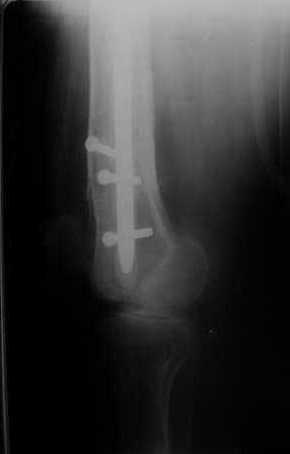

В остальном, операция прошла без технических трудностей. Александр Николаевич, спасибо за ваши прекрасные развертки. Так не хочется отдавать их Вам обратно! Завтра пациент выписывается. Температура тела и анализы у него нормальные. Бедро мягкое, отечность тканей значительно уменьшилась. Послеоперационные раны зажили первичным натяжением. Укорочение конечности составляет 1,5 см (по ощущениям больного, это оптимальная длина ноги для него, так как у него анкилоз коленного сустава и голеностопного сустава в положении подошвенного сгибания). Пациент ходит с дозированной нагрузкой на конечность (10% от веса тела). Свищ на передне-наружной поверхности средней трети бедра, который открылся за неделю до последней операции рядом со стержнем аппарата, закрылся 5 дней назад (рис. 6,7, 8).

>Свищ на передне-наружной поверхности средней трети бедра, который открылся за неделю до последней операции рядом со

>стержнем аппарата, закрылся 5 дней назад (рис. 6,7, 8).